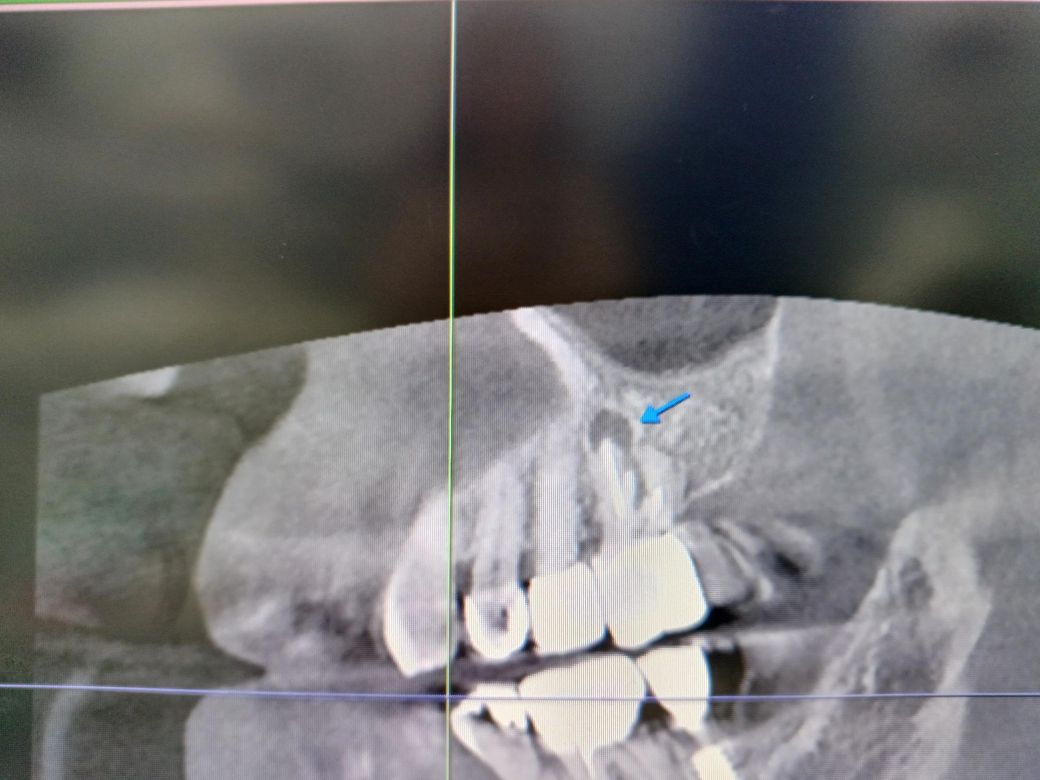

신경치료 후 크라운 장착한 치아뿌리 염증상태 입니다 잠잘때는 통증이 거의 없는데 일어나서 일상 중 통증이 있으며 말을할때 더 아픕니다 염증이 크기가 저정도면 큰편인지 저정도면 발치해야 되는지

저 치아가 옆주변 치아에도 영향을 주는지 문의드립니다

사진으로봤을 경우에는 치근단에 병소가 생긴것으로 보입니다.

근단부위의 염증은 신경관의 감염으로 생기기 때문에 재신경치료를 해주는것이 좋을수 있습니다 .

염증이 잇다고 해서 무조건 문제가 되는건 아니지만 증상이 잇다면 재신경치로 또는 발치를 해야될것같습니다. 아직 활성화가 많이 된건 아니라서 재신경치료를 한번 상담받아보세요.

옆치아에 영향을 줄 수 있으며 염증이 큰 편이기때문에, 발치를 하셔야 할 것으로 보입니다.